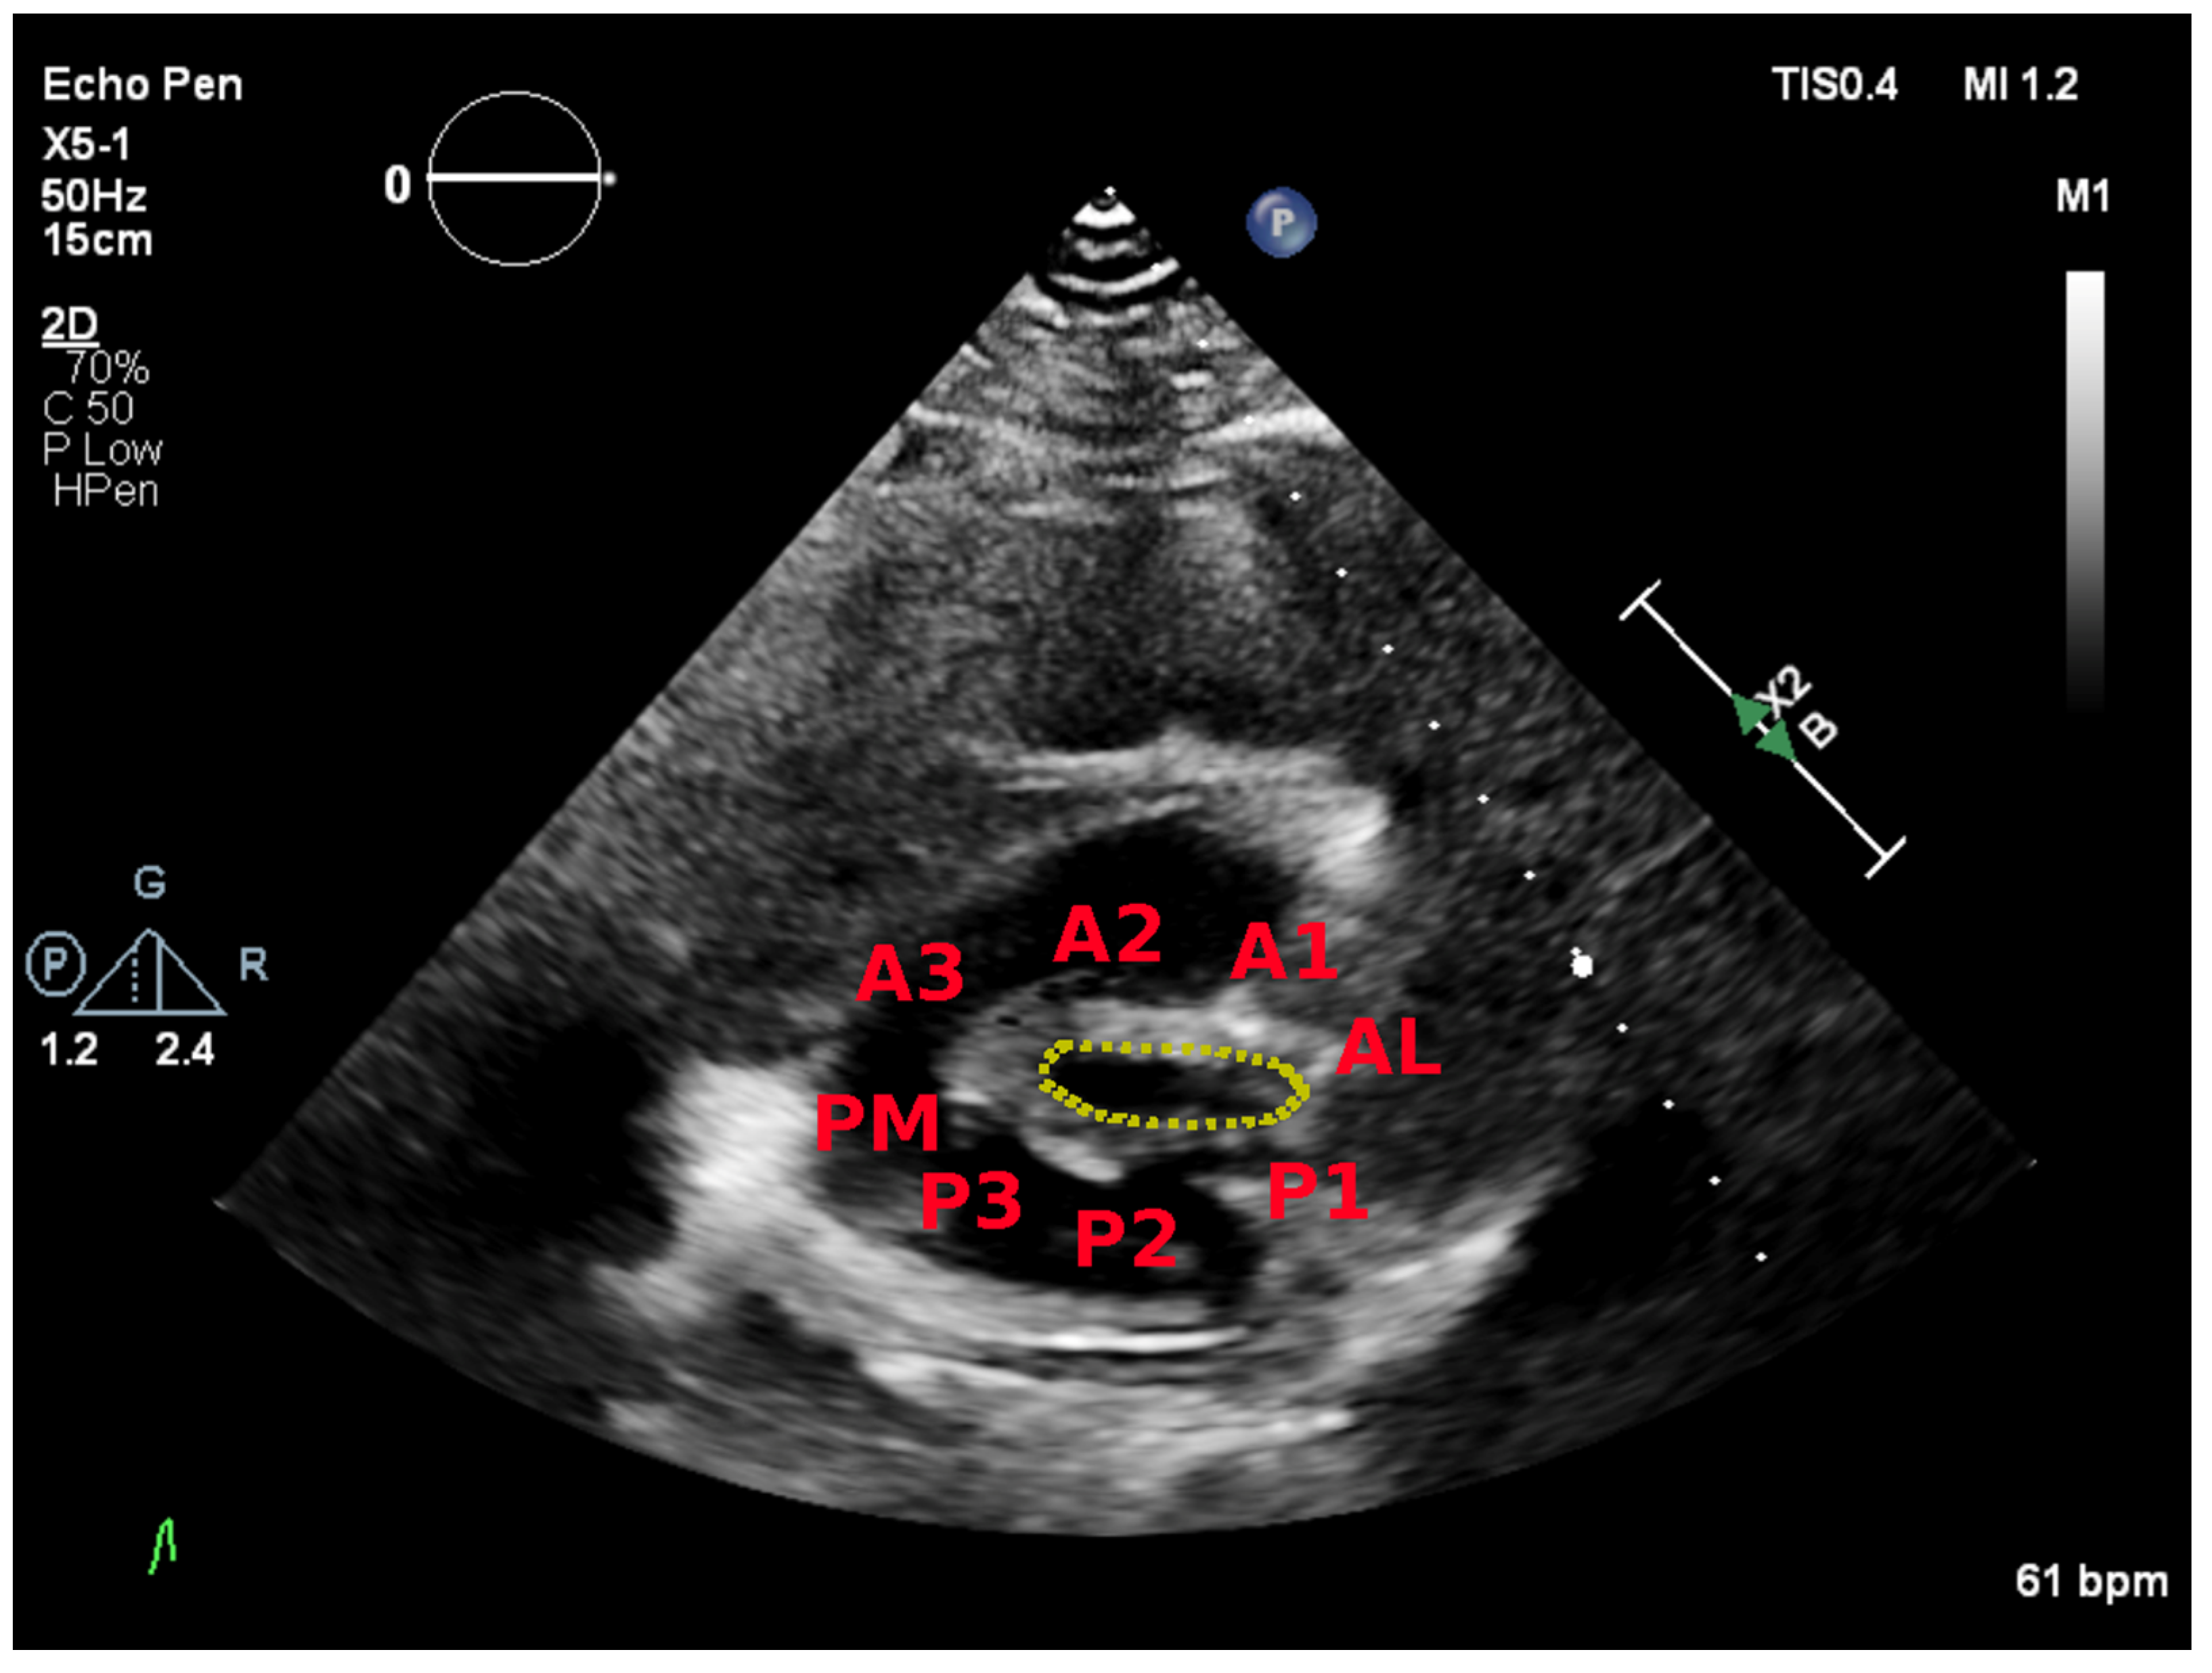

| Anterior Leaflet | Posterior Leaflet | |||||

| Thickness (0–6) (0 = normal, 1 = thickened) | A1 | A2 | A3 | P1 | P2 | P3 |

| Mobility (0–6) (0 = normal, 1 = limited) | 0–1 | 0–1 | 0–1 | 0–1 | 0–1 | 0–1 |

| Calcification (0–10) (0 = no, 1–2 = calcified) | 0–2 | 0–1 | 0–2 | 0–2 | 0–1 | 0–2 |

| Subvalvular Apparatus | ||||||

| Proximal Third | Middle Third | Distal Third | ||||

| Thickness (0–3) (0 = normal, 1 = thickened) | 0–1 | 0–1 | 0–1 | |||

| Separation (0–6) (0 = normal, 1 = partial, 2 = no) | 0–2 | 0–2 | 0–2 | |||